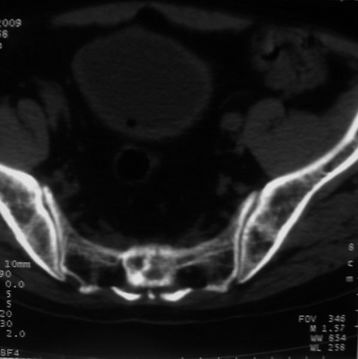

1)考虑前列腺增生症并阻塞性膀胱炎。2)骶椎右侧类似囊状骨质密度减低区,边缘骨质硬化,其内为软组织密度影填塞,相邻之骶椎椎管受压变形;考虑为骶椎右侧囊肿或神经纤维瘤。

建议:行mri检查。

骶椎脊索瘤

1)前列腺明显增大,突入膀胱,各叶比例协调,密度均匀,精囊腺及精囊角正常;考虑前列腺增生症并阻塞性膀胱炎。2)骶椎右侧类似囊状骨质密度减低区,边缘骨质硬化,其内为软组织密度影填塞,相邻之骶椎椎管受压变形;考虑为骶椎右侧囊肿或神经纤维瘤。

建议:行mri检查